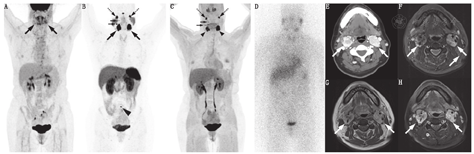

用于HNPGL分期、确定病变范围和治疗决策的一线显像方法通常为解剖成像,如MRI、MR血管造影、CT和CT血管造影[60]。在CT图像上(图3),HNPGL血管丰富,早期动脉期强化明显,在增强MRI上亦是如此,常呈"椒盐"征。MRI和MR血管造影通常用于确定受累程度、疾病管理支持、风险评估和预后评估。MRI涉及一系列耗时的序列。一项SDHx相关的HNPGL前瞻性研究将序列限制为短对比增强MRI方案,包括三维飞行时间MR血管造影序列和具有脂肪饱和的轴位平面快速自旋回波T1加权序列。上述序列识别HNPGL的灵敏度和特异性分别为88.7%和93.7%[61]。

68Ga-DOTA-SSA、18F-FDOPA和18F-FDG显像(较小程度上)诊断HNPGL具有高灵敏度(图3),而123I/131I-MIBG的灵敏度较差(10%~42%)(图3;表3)。68Ga-DOTATATE对HNPGL的灵敏度为100%,可检出其他显像无法检出的额外病变[52]。18F-FDOPA的灵敏度也很高(97%);对于头颈部以外病变,18F-FDOPA仅检出60%,18F-FDG仅检出70%,CT或MRI仅检出77%,而68Ga-DOTATATE可检出100%[52]。

18F-FDOPA对HNPGL的灵敏度较高(86.7%~100%)[23,31,32,50,62,63],超过MRI(表3)[50,62,63]。此外,18F-FDOPA比MR血管造影更具可重复性,且通常能比MRI提供更多信息,尤其对于可能会被遗漏的病灶[50,63]。18F-FDOPA被认为是HNPGL的一线显像手段,尽管最新研究显示68Ga-DOTA-SSA的效果更优[25,35]。

18F-FDG在HNPGL中的灵敏度为71%~90.5%[52,62,64],低于68Ga-DOTA-SSA或18F-FDOPA。有研究报道,在独立HNPGL患者组中,18F-FDG PET/CT基于病灶灵敏度为71%,而18F-FDOPA可达97%[52]。

综上所述,对于HNPGL或HNPGL高风险的患者,功能显像具有较高的灵敏度,应与MRI结合使用,后者用于手术和治疗决策。在绝大多数情况下,68Ga-DOTA-SSA被认为是首选,其次是18F-FDOPA,再次是18F-FDG(图4)。